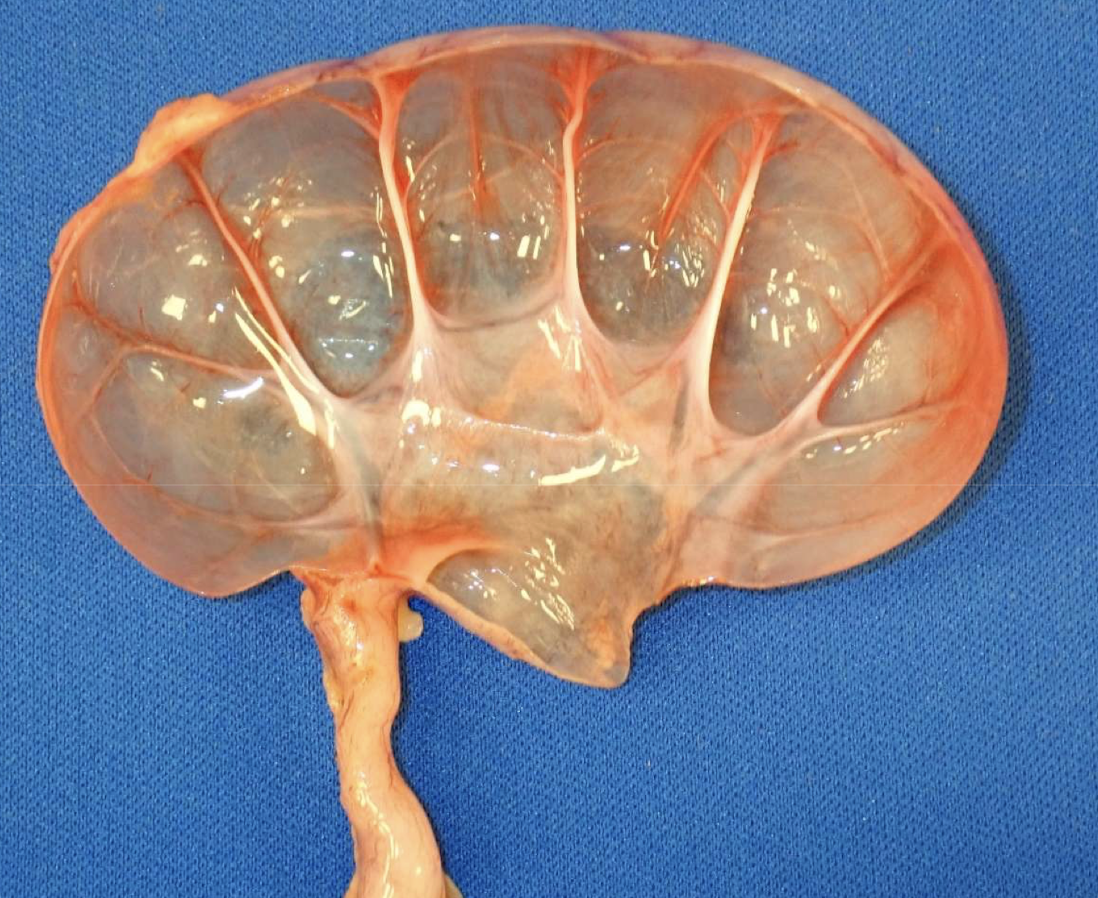

What complications are shown in the necropsy images related to urinary obstruction?

Marked hydronephrosis

Hydroureter

Severe bladder distention

Consequences of prolonged obstruction → pressure atrophy and renal damage

What does hydronephrosis look like grossly?

Dilated renal pelvis

Thinned cortex

Progressive pressure atrophy

no room to expand due to the fixed cortex, fluid accumulates in the kidney. kidney does not have a shut off system and will continue producing urine